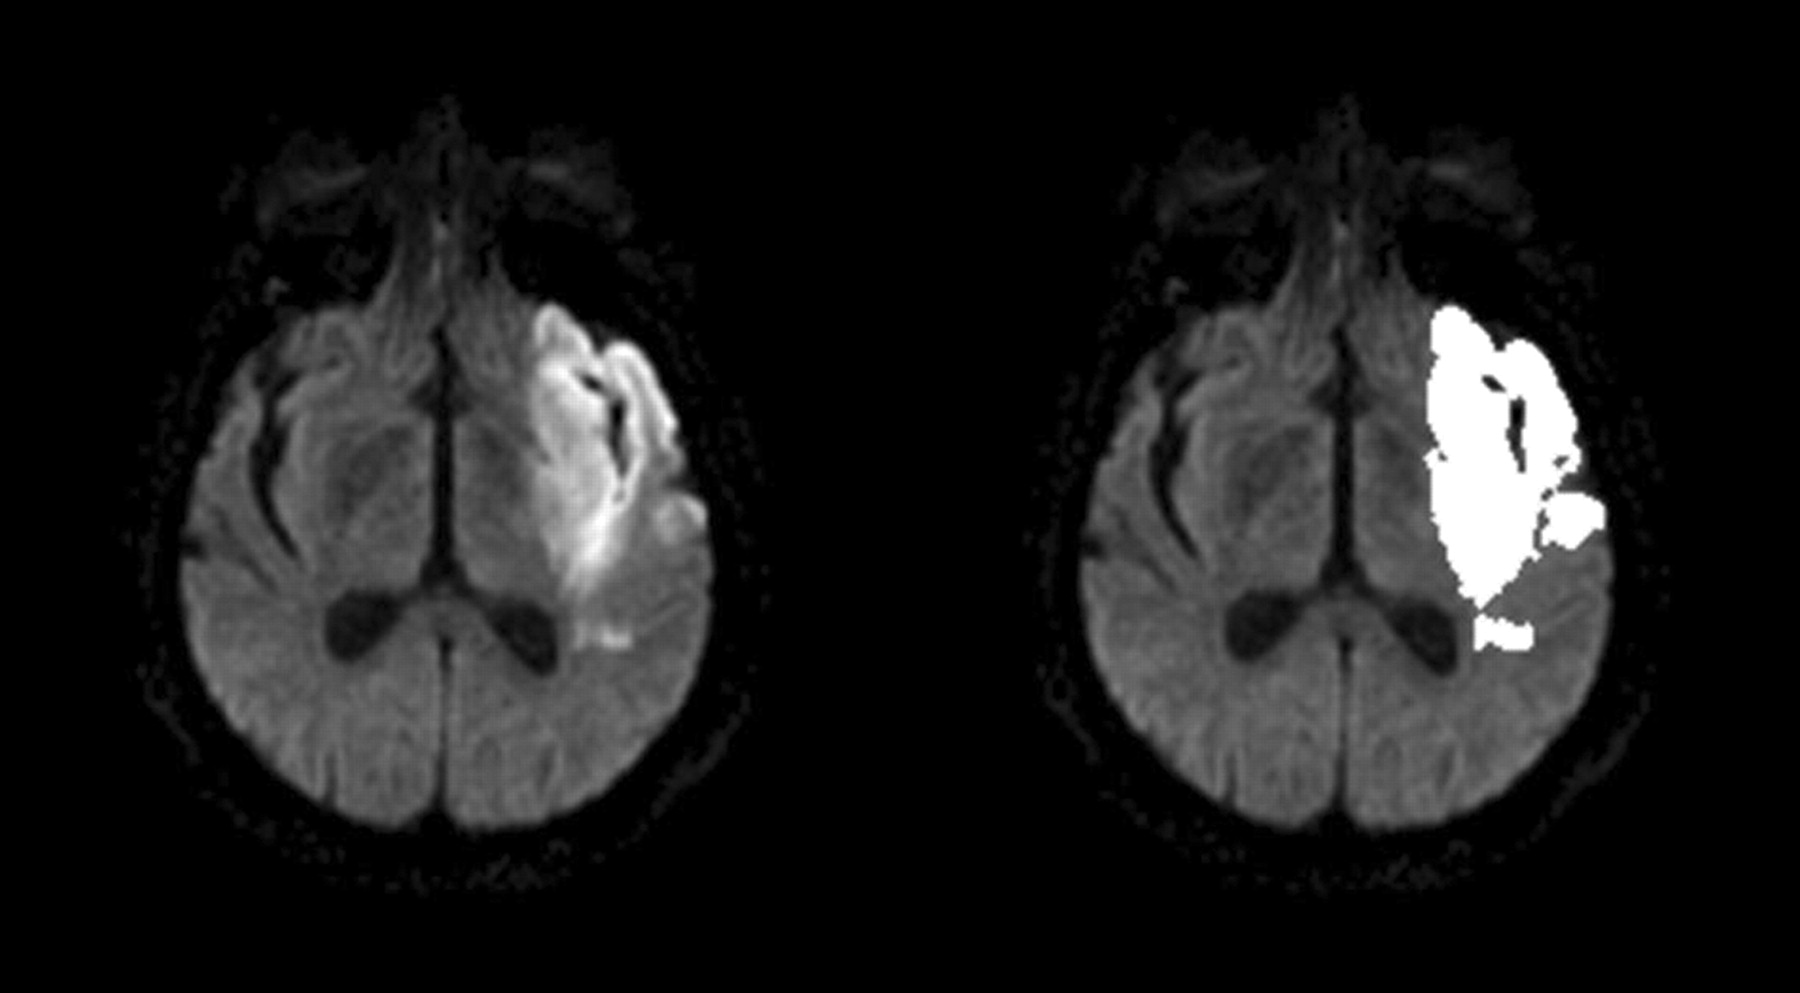

Images demonstrate the region >2 SDs above the mean abnormal restriction. Left, diffusion-weighted image (b=1000 s/mm2). Right, Mask.

Images with decreased signal intensity and the region with >30% decrease compared with normal brain parenchyma. Left, ADC images (b=0 s/mm2). Right, Resultant mask.